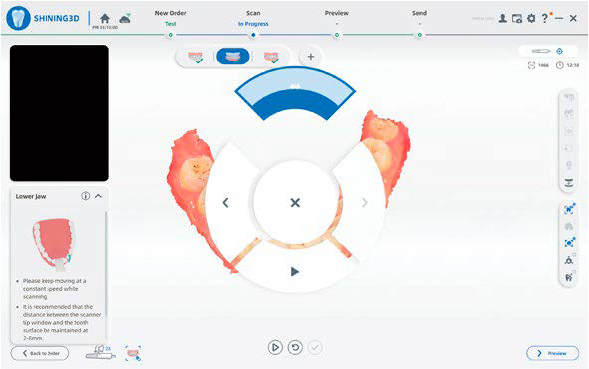

INTERFACCIA INTUITIVA

Un design pulito e lineare per un processo di scansione più efficiente e senza interruzioni.

CONTROLLO CONTACTLESS

Il sistema di motion sensing consente di gestire la scansione senza contatto, migliorando igiene e praticità.